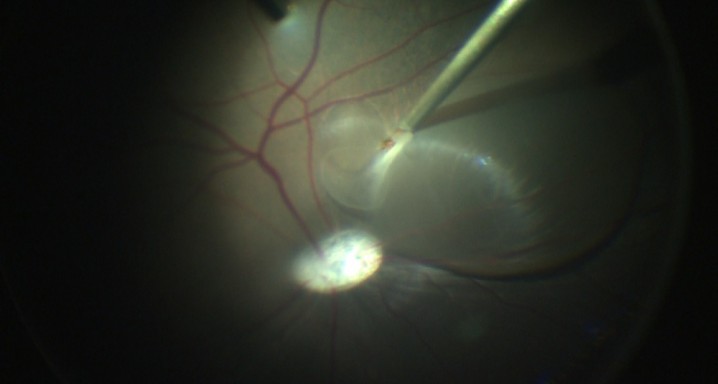

To date, gene therapy or growth factor supplement strategies cannot regenerate retinal pigment epithelial (RPE) cells loss in degenerative retinal diseases. Cell therapy replacement strategies such the use of fetal tissue or embryonic stem cells (ESCs), are still subject to ethical concerns and the tumorigenic-associated responses linked to the use of fetal material. The main goal of this project is to identify the best method of differentiation from patient cells towards functional RPE and PR cells and to implant them in an animal model of geographic atrophy of the retina. The development of such technologies will allow the initiation of a phase I clinical trial in a-AMD, retinitis pigmentosa and Stargardt’s disease patients.